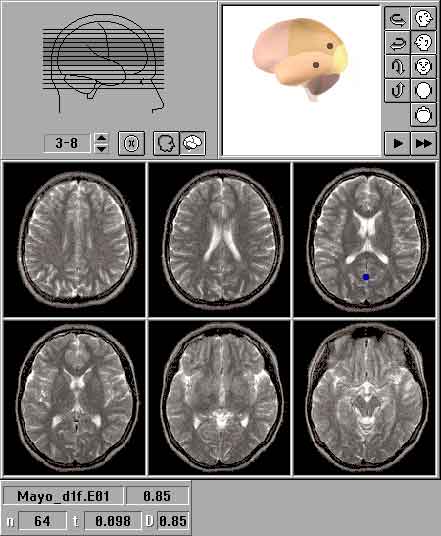

Для топографического картирования ЗВП использовали специализированный комплекс "МБН-нейрокартограф" (МБН, г. Москва). Комплекс состоит из фотостимулятора ФСТ-01, 16-канального усилителя УБПЭЭГ-01, аналого-цифрового преобразователя, электродов для электроэнцефалографии с устройством их фиксации, блока питания ИБП-01 и программных средств для анализа и картирования электрической активности головного мозга, и функционирует на базе IBM-совместимого персонального компьютера.

Оценивали конфигурацию, латентность и амплитуду компонентов P2 вспышечных ЗВП в затылочных отведениях (O1, O2). Изучение потенциальных полей ЗВП проводили по топографическим картам, на которых, с использованием принципа цветового кодирования, отображались мгновенные значения потенциала. На топографических картах, соответствующих компонентам P2, отмечали наличие и взаимное расположение позитивных и негативных областей, их конфигурацию, межполушарную асимметрию, наличие доминирующих центров активности.

Расположение источника (генератора) ЗВП и место регистрации наибольшего значения потенциала на поверхности головы нередко не совпадали, что некоторыми авторами объясняется различной ориентацией источников ЗВП и наличием у мозга, его оболочек и ликвора свойств объемного проводника [1,2,9]. Для уточнения данных топографического картирования использовали метод трехмерной локализации дипольных источников ЗВП, предназначенный для компьютерного моделирования расположения доминирующих центров биоэлектрической активности в структурах мозга [1,2,9,16,17]. Трехмерная локализация источников ЗВП осуществлялась с помощью компьютерной программы "Брейнлок 5.0" (автор Коптелов Ю.М.). В качестве входной информации, как и для топографического картирования, использовали многоканальную запись ЗВП. Дипольные источники ЗВП изображались на ортогональных проекциях головы в виде ''стрелок'' с основанием в центре вычисленного диполя. ''Стрелки'' направлены от "минуса" диполя к его "плюсу". Также источники выводились на семь схематических изображений срезов головного мозга, сделанных в орбито-миотальной проекции. Для улучшения объемного представления источники изображались внутри трехмерной вращающейся модели головного мозга. При наличии файлов магнитно-резонансной томографии локализация проводилась с учетом реальной топографии структур мозга пациента.

Рис.1. Топографическое картирование

Контрольная группа (практически здоровые). У всех исследованных доминировала активность теменно-затылочных отделов мозга, что проявлялось соответствующим расположением позитивных зон и локализацией источников вспышечных ЗВП. Позитивные зоны были отмечены в обеих затылочных областях с амплитудным преобладанием в одной из них, или в одной из теменно-затылочных областей, чаще в контралатеральной по отношению к стимулируемому глазу (Рис. 1). Преобладание биоэлектрической активности в контралатеральной затылочной области при стимуляции всего поля зрения (full-field) ряд авторов объясняли особенностями количественного распределения нервных волокон в хиазме, вследствие чего больше волокон проводит афферентные импульсы в контралатеральное по отношению к стимулируемому глазу полушарие, чем в ипсилатеральное. Интериндивидуальная вариабельность выраженности и топографии компонента P2 отмечалась многими исследователями [1,8], что объяснялось значительной вариабельностью асимметрии затылочной коры, положения стриарной коры и ее погружения в борозды [12,18,19]. Иногда регистрировались низкоамплитудные позитивные зоны в лобных областях (чаще в ипсилатеральной). В литературе дискутируется возможная связь колебаний биопотенциала в лобной области с электроретинограммой и электромиографическими артефактами, возникающими при сокращении наружных мышц глаза и смаргивании (Rubinstein M.P., Harding G.F.A., 1981). У некоторых испытуемых отмечались позитивные очаги в височных областях, что, возможно, объясняется регистрацией артефактов слуховых ВП на щелчки фотостимулятора или миограммы. Эквивалентные источники биоэлектрической активности локализовались в затылочных отделах мозга, в области стриарной коры или клина, чаще с контралатеральной стороны (Рис. 2). В некоторых случаях источники были локализованы не в затылочных, а в теменных долях мозга. При наличии двух источников одновременно, один из них локализовался в затылочной или теменной доле, другой - в лобной или височной доле мозга.

Рис.2. Локализация источников вспышечных ЗВП в норме: ортогональные проекции